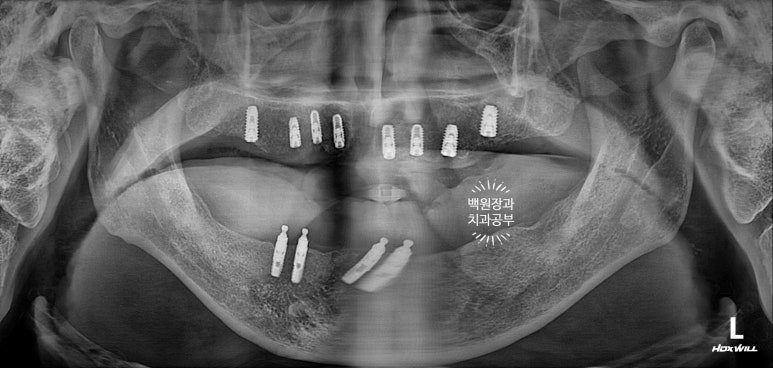

위턱 임플란트를 먼저 심어드렸습니다.

그리하여 임플란트 주변 뼈이식술과 상악동 뼈이식술을 동반해서 위턱에 임플란트 8개를 먼저 심어드렸습니다.

약 3주 뒤 아래턱 임플란트를 심어드렸습니다.

그리고 약 3주 뒤에 오스템임플란트 네비게이션 임플란트 시스템을 이용하여 아래 임플란트를 심어드렸습니다.

아래턱에서는 임플란트 주위염이 심했던 왼쪽 아래 임플란트 하나를 제외한 3개를 사용하기로 하여서, 4개만 추가로 심기로 하였고 위턱은 총 8개를 심어드리기로 계획하였습니다.

전체 틀니와 임플란트 틀니에서 전체 임플란트로 바꾸기 위해 총 12개의 임플란트를 추가로 심게 되었네요.